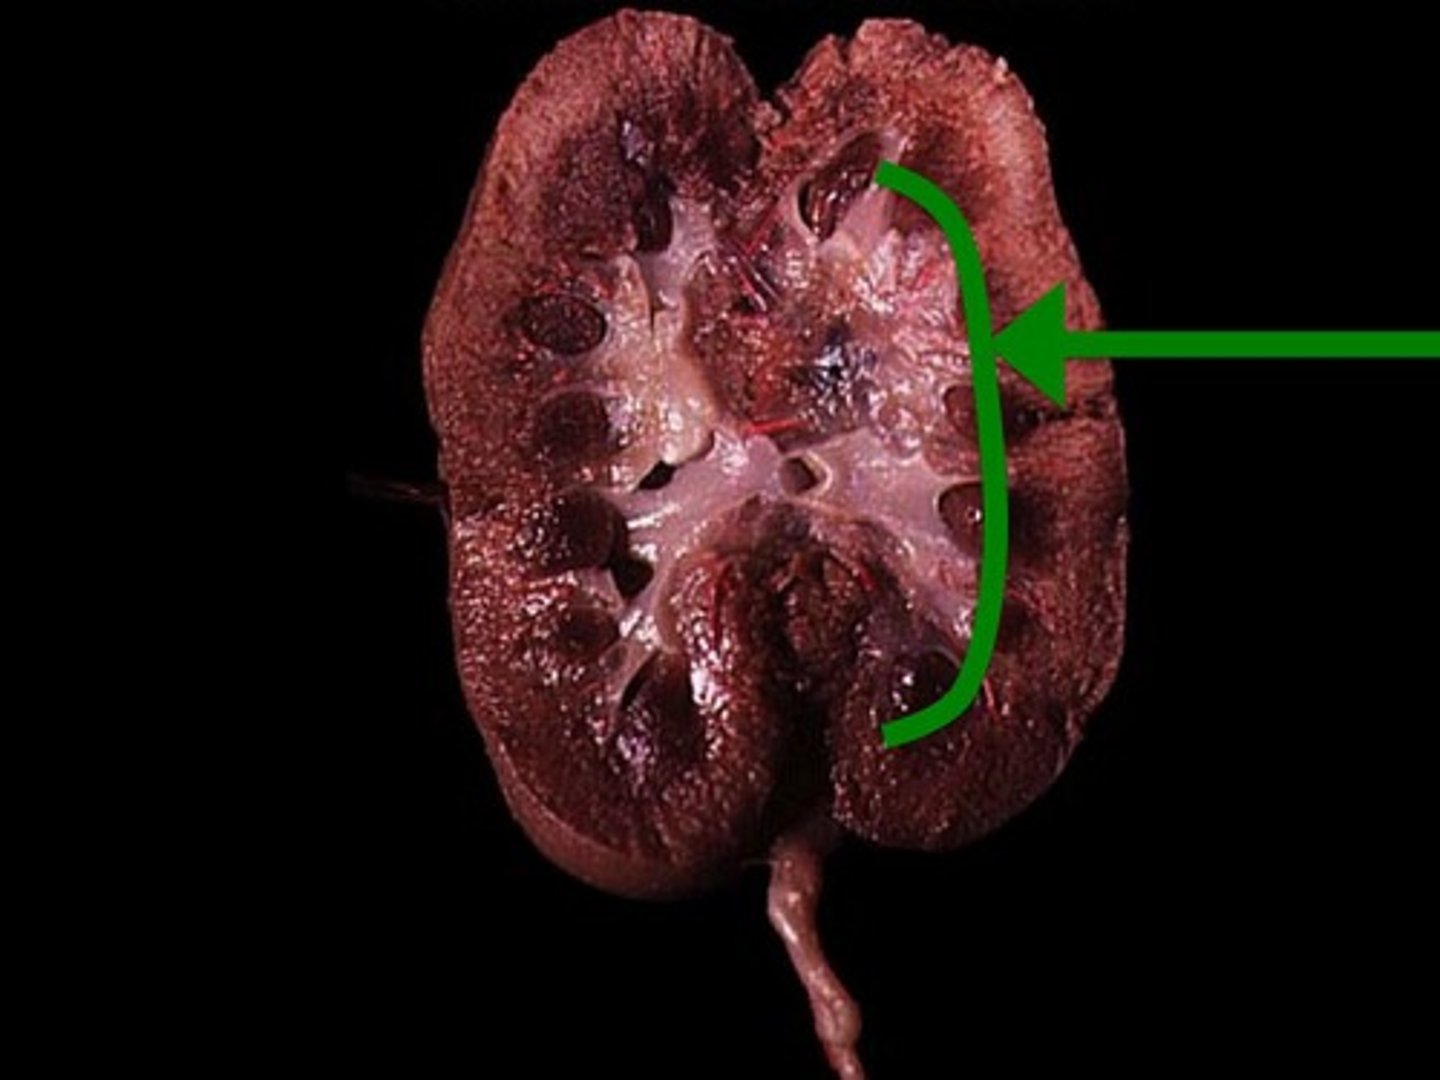

Renal Cortex

Renal Medulla

Renal Pyramid

Renal Column

Renal Pelvis

Ureter